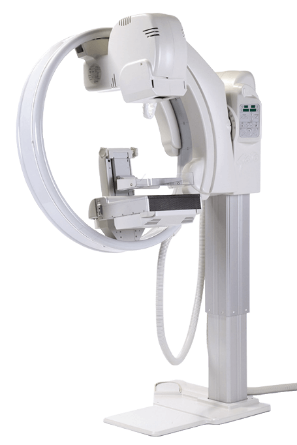

Шаг 5. Снимочный штатив

Подавляющее большинство маммограф выполнены на снимочном штативе С-образной формы.

У некоторых производителей снимочные штативы имеют иные формы, встречаются кольцеобразные и еще реже горизонтальные штативы.

У кольцеобразного штатива есть возможность перемещения во всех трёх плоскостях.

Передне-наклонная проекция (ПКП или FOA) на маммографе с кольцеобразным штативом увеличивает площадь снимка в среднем на 2 см. На снимке появляется ретромаммарное пространство, где часто определяется рак молочной железы.

С-образный штатив / Кольцевой штатив